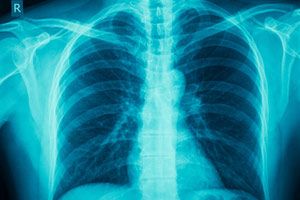

Ученые раскрыли тайну астмы, которая поражает женщин вдвое чаще, чем мужчин

Астма гораздо чаще поражает женщин, так как их половые гормоны не блокируют воспаления и не замедляют выделение слизи легкими – за эту функцию отвечает "мужской гормон" тестостерон.

Напомним, что астмой называют хроническое воспаление органов дыхания, которое выражается в приступах удушья различной силы и продолжительности. Причиной заболевания ученые считают нарушения в работе клеток иммунной системы, которые вызывают воспаления в дыхательных проходах и заставляют их сужаться.

По оценкам Всемирной организации здравоохранения (ВОЗ), в мире насчитывается 300 миллионов человек, страдающих астмой, и каждое десятилетие их количество возрастает в полтора раза. Результаты исследований, проведенных французскими и испанскими медиками, свидетельствуют о том, что женщины страдают от астмы примерно в два раза чаще мужчин и их чаще поражают тяжелые формы болезни.